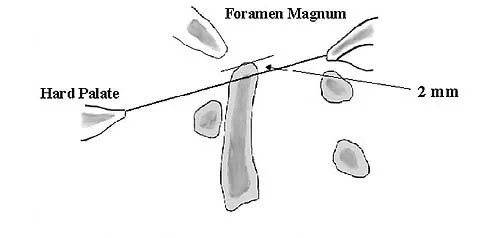

The illustration shown in Figure 19 shows a Chamberlain line. What is the most likely diagnosis?

Correct Answer: Normal findings

Explanation:

Basilar invagination is best defined as vertical or compressive instability at the occiput-C1 joint. Such invaginations most commonly occur in patients with rheumatoid arthritis but also can occur secondary to trauma or tumor. A Chamberlain line is used as a method to determine basilar invagination. The odontoid tip should not be more than 5 mm above a Chamberlain line. Wiesel SW, Rothman RH: Occipito-atlantal hypermobility. Spine 1979;4:187-191.